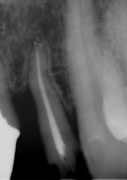

虫歯はじっとしていても痛むような大きさになると、虫歯菌が歯の神経の中に入ってしまい、神経をとらないと痛みが取れません。ところが神経をとった歯の空洞で細菌が繁殖すると人間の免疫力が働かないため、細菌はどんどん増殖して、化膿して「歯が浮いて痛くて噛めない」という状態になります。したがって、細菌が繁殖しないように細菌の繁殖元となる死んだ神経をきれいに取り、細菌の住める空洞をなくすために、緊密に神経をとった根の穴を埋める必要があります。しかしながら、歯の神経の形態は複雑で、時に湾曲したり、枝別れしたりしています(図1)。

図1